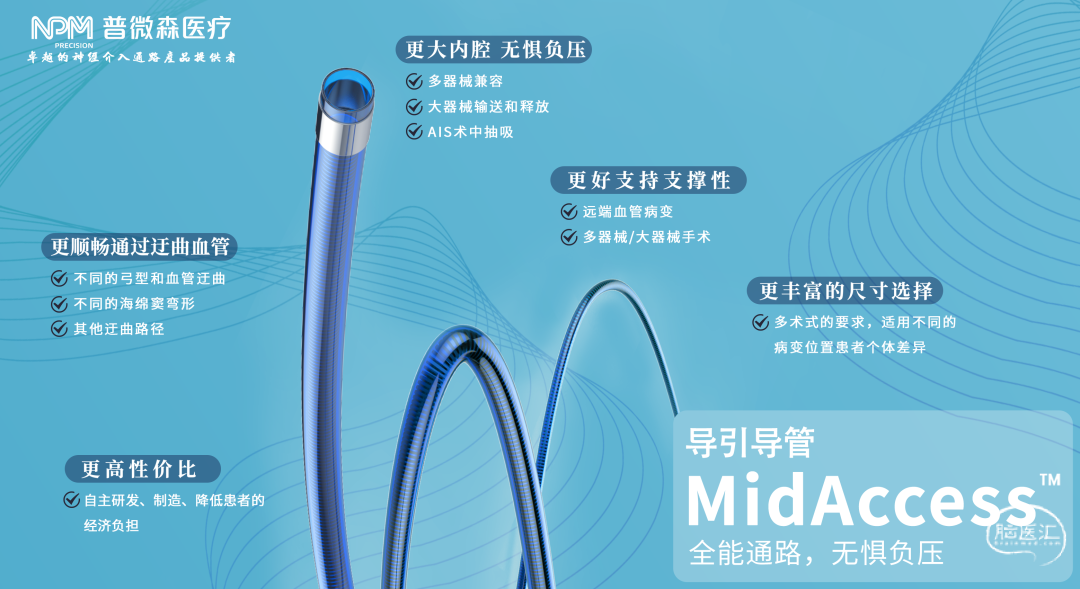

•GC-088-90普微森MidAccess™导引导管

•GC-060-125普微森MidAccess™导引导管

GC-088-90普微森MidAccess™导引导管:前端柔顺,整体支撑强,可以顺利输送到椎动脉V2段,并提供有效的支撑,在该病例中起到了支撑导管的作用。

GC-060-125普微森MidAccess™导引导管:良好的通过性,可以顺畅送至血管远端,拥有更大的抽吸力及血栓抓取力,减少了血栓逃逸,帮助实现了快速再通。